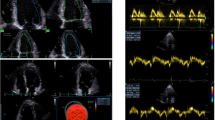

Extended Data Fig. 1 Representative magnetic resonance images of a symptomatic patient.

(a-f) Late gadolinium enhancement imaging (A, D-F) and Native T1 (B) and T2 (C) mapping measurements of a 57-year-old woman evaluated 201 days after COVID-19 infection. This individual reported dyspnea, palpitations, and chest pain, worsening on minimal exertion. Late gadolinium enhancement imaging allows to visualize regional accumulation of the gadolinium-based contrast agent along the outer rim of the myocardial free wall (red arrows), as well as within the thickened pericardial layers, separated by small amounts of pericardial effusion (blue arrows).